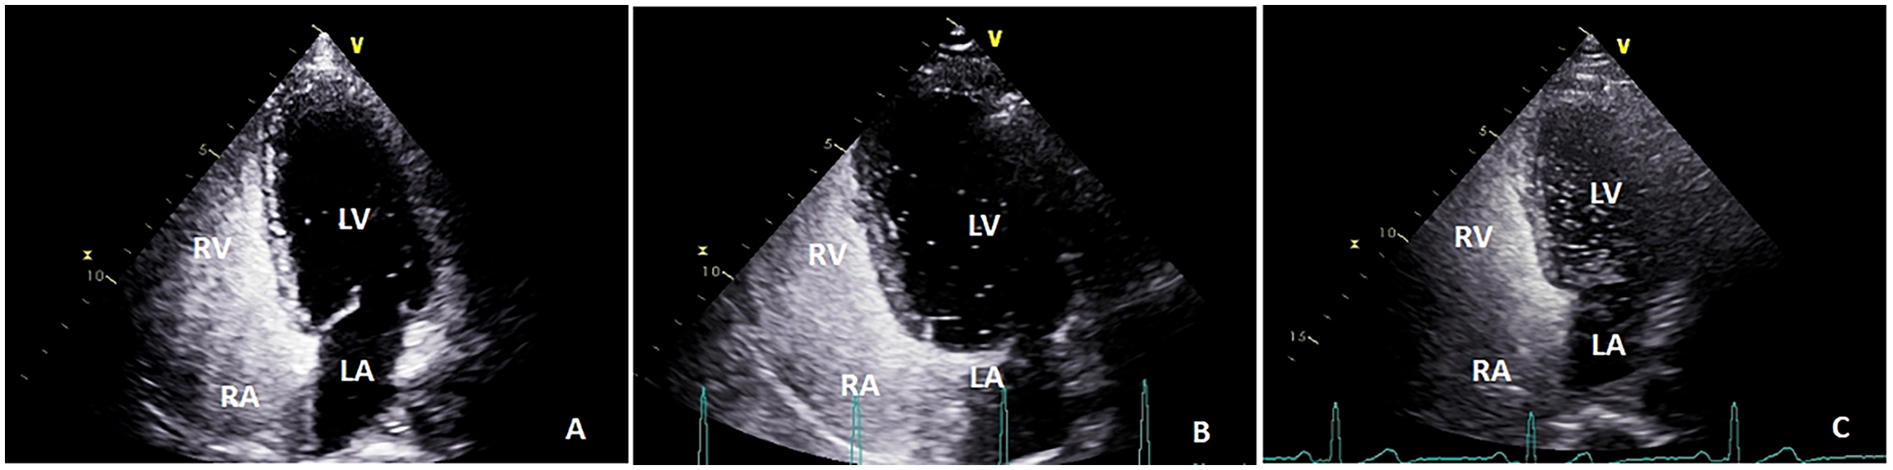

Color Doppler ultrasound diagnostic apparatus (model: Vivid™E9, which has an M5S probe frequency of 1.5–4.5 MHz) was utilized to examine right-to-left shunts. Saline microbubble contrast agent was prepared as follows: 8 mL of 0.9% saline was drawn into one 10 mL syringe and 1 mL of air into another 10 mL syringe, after which these syringes were connected to two of the ports of a medical three-way valve. The third port was connected to a scalp needle for cubital vein puncture. After successful puncture, about 1 mL of the examinee's venous blood was drawn into the syringe containing 8 mL of normal saline. After adjusting the three-way valve, the 1 mL of air and the 8 mL of normal saline and blood were thoroughly mixed by quickly pushing the syringes’ contents back and forth approximately 21 times and the resultant mixture injected into the patient's cubital vein. The patient was then placed in a left lateral decubitus position and injected with contrast medium at rest and performing the Valsalva maneuver, the interval between these two injections being more than 5 min. The number of microbubbles in the left atrium (right-to-left shunt) during the five cardiac cycles after right atrial echocardiography was counted via a transthoracic apical four-chamber view. The findings were classified as follows: negative, small (<10 microbubbles), medium (10–30 microbubbles) and large (>30 microbubbles) (30) (Figure 3). This procedure was carried out with TTE whenever possible because Valsalva maneuvers are easier to perform during TTE (31).

Figure 3

The number of microbubbles in left atrium (right-to-left shunt) during the five cardiac cycles after right atrial echocardiography was observed by transthoracic apical four-chamber view: (A) small (<10 microbubbles); (B) medium (10–30 microbubbles); and (C), large (>30 microbubbles); LA, left atrium; RA, right atrium; LV, left ventricle; RV, right ventricle.